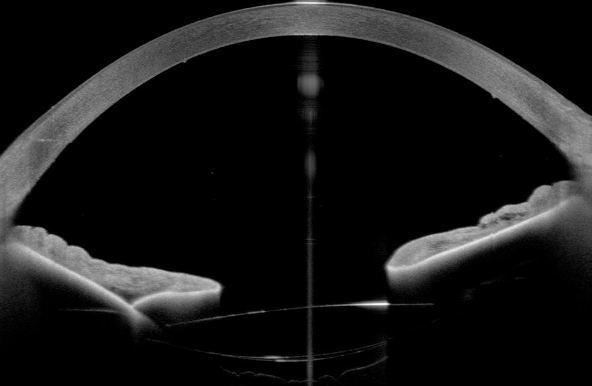

A 71-year-old patient presented after complicated cataract surgery with decreased visual acuity and cloudy vision. On examination, best corrected visual acuity was 1.5 logMAR. Slit-lamp examination revealed diffusely epithelial and stromal edema with Descemet folds centrally and DMD. A high-resolution swept-source OCT (Anterion, Heidelberg Engineering, Heidelberg, Germany) was used to better evaluate and visualize the extent of DMD. Figure 1 [Fig. 1] shows a slit-lamp image of the eye and Figure 2 [Fig. 2] shows the anterior segment OCT. The OCT shows a significantly centrally detached Descemet membrane (DM) towards the anterior chamber. Pre-operatively endothelial cell count could not be measured due to significant corneal edema. We decided to perform a complete anterior chamber air tamponade under topical anesthesia and eventually reduced the air bubble to 80% anterior chamber volume after one hour. On the first day postoperatively, central corneal edema decreased, visual acuity improved to 0.30 logMAR and anterior segment OCT showed a fully attached Descemet membrane. Mean postoperative endothelial cell count after day 1 was 1,149 cells/mm2. After 3 months visual acuity further improved to 0.1 logMAR, with no central corneal edema (Figure 3 [Fig. 3]) and normal intraocular pressure. The OCT shows a fully attached DM (Figure 4 [Fig. 4]).

Figure 2: High-resolution anterior segment OCT showing a significantly centrally detached Descemet membrane towards the anterior chamber